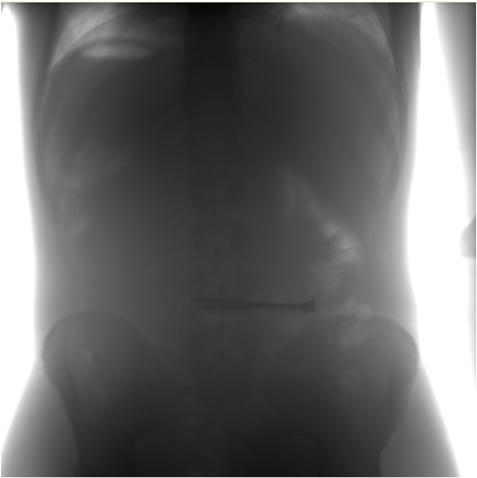

Пример сырого снимка и после обработки, на самом деле оригинальный фаил весит около 14,5 мб и его нужно смотреть на рентгенологическом мониторе, а после конвертации в бытовые форматы и сжатия информативность в разы уменьшается.